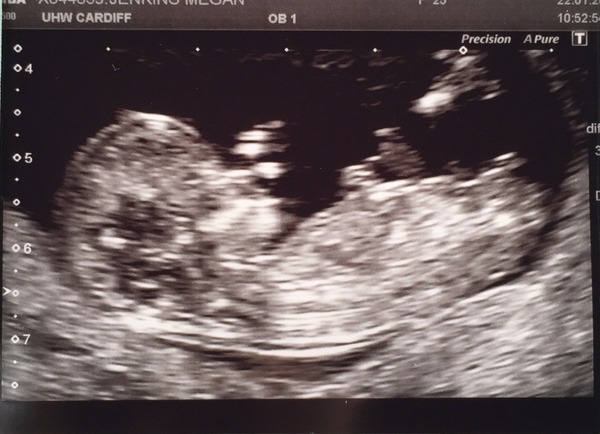

bear and Showgirl fab pics, it's so lovely to see baby and amazing how much they do even at this early stage! I'm guessing girls for you both